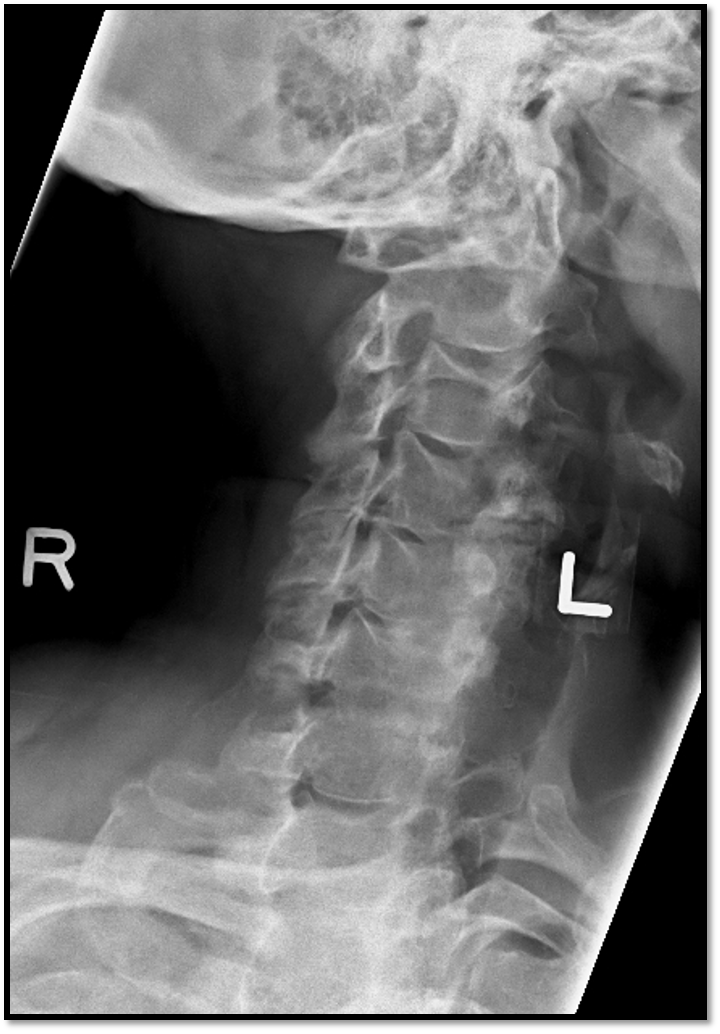

3

Q

A

• rotation and tilt issue

• swimmers not needed (fusion of C6/C7)